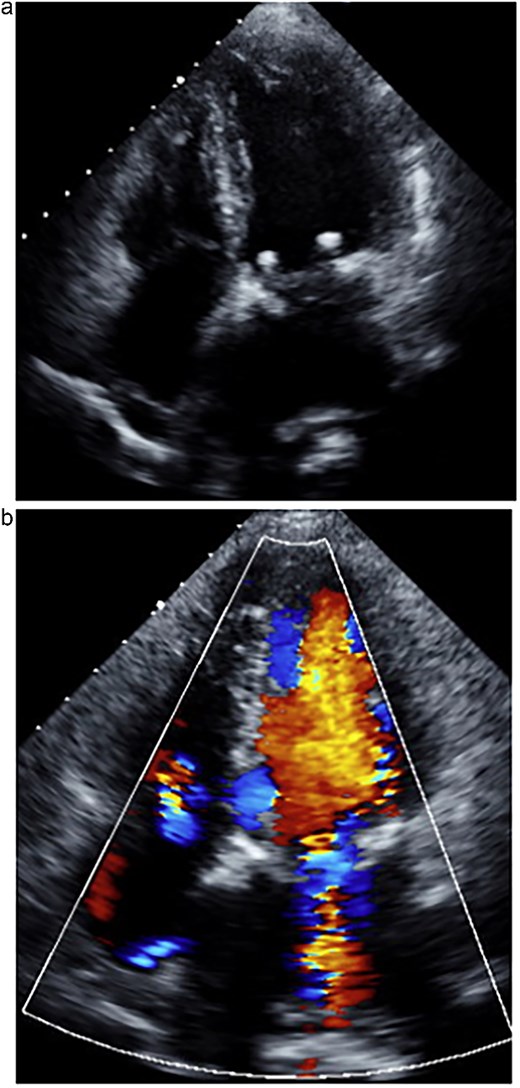

Considering the persistent MR and the patient’s preserved general condition despite her frailty, MICS-MVR was performed via a right fourth intercostal space mini-thoracotomy. Cardiopulmonary bypass was established with femoral artery and vein cannulation. Intraoperative findings revealed a severe laceration extending from the A3 to P3 segments, with prolapse of A3 and two tears near the annulus on P3. A bioprosthetic mitral valve (Epic 29 mm; Abbott, Abbott Park, IL, USA) was implanted under direct vision (Fig. 2).

Intraoperative findings during minimally invasive mitral valve replacement. (a) Prolapse of the A3 segment and two tears in the P3 segment were observed. (b) Valve replacement was performed using a 29-mm Epic bioprosthesis.